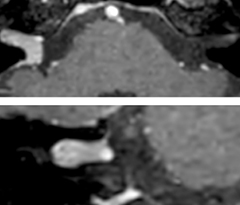

The 3D TSE T1w black blood MSDE sequence with fat suppression has an isotropic 0.8 mm voxel size and sagittal oblique and axial reformats are made. The images show superficial temporal artery thickening and peri-arterial fat infiltration. The 3D TSE PDw black blood MSDE with fat suppression has 0.55 mm isotropic voxels. The images shows focal involvement of the frontal branch of the superficial temporal artery.